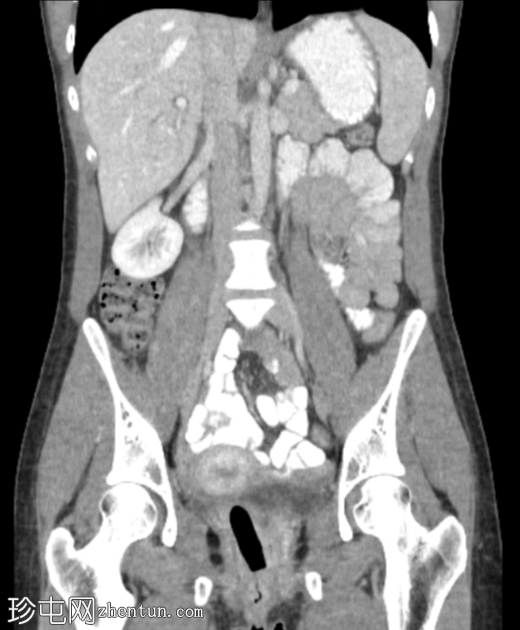

冠状位增强扫描(门静脉期)

3.png

定位片、轴位、矢状位及冠状位图像均可见阴道内有一根线状充气棉塞。棉塞的线头在本例中清晰可见。

肝脏轻度肿大,伴门静脉周围水肿及液性密度影,与临床高度怀疑急性肝炎相符。

阴道内有一根棉塞(女性卫生用品),是月经期女性在X线检查中常见的偶然发现。它们由棉和人造丝制成,容易滞留空气,因此在影像检查中,它们会呈现出阴道的形状和方向。有时,也能看到卫生棉条的线,就像本例中一样。放射科医生应该能够识别阴道卫生棉条,以免将其与病变混淆。